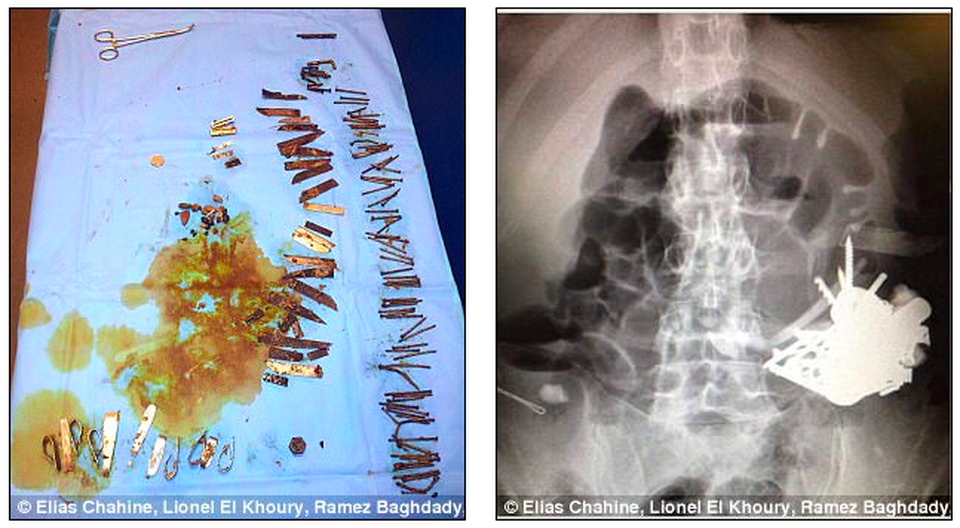

(Dân trí) - Các bác sĩ vừa lấy ra hơn 100 mẩu kim loại từ dạ dày một người đàn ông sau khi anh này nuốt ghim, kim và cán thìa.

Và giờ đây, khi các mẩu kim loại này kết lại với nhau, tạo thành các khối ở nhiều vị trí trong đường tiêu hóa, bao gồm cả dạ dày.

Các khối kim loại kết dính với nhau trong bụng bệnh nhân

Bệnh nhân này cũng đã trải qua 5 lần mổ để lấy móng, đinh vít, dao, các ốc vít, cán thìa, lọ muối, miếng cọ rửa, dây sắt và đồng xu bị nuốt vào bụng.